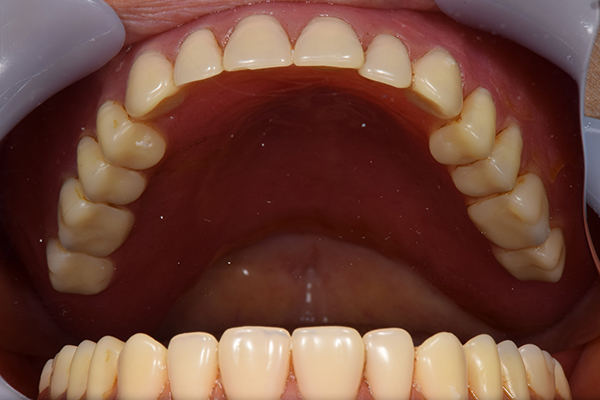

ケース3(インプラントを用いた部分入れ歯)

右上と左下の歯がない方です。 上の入れ歯の安定が悪く、作り直したいとのことでいらっしゃいました。 今お使いの上の入れ歯を見てみると、口蓋部分が抜けており、安定性に欠ける構造になっていました。この入れ歯はノンメタルクラスプデンチャーといって、金属のバネを使用しない 入れ歯になります。これは見た目は良いのですが、歯への負担が大きいことと、入れ歯自体がやわらかいため、噛むには不便なことがあります。

入れ歯は極力薄くするために金属を使用しました。しっかり噛める様にするため、ノンメタルクラスプデンチャーにはしませんでした。

上の入れ歯(表)

上の入れ歯(裏)

下の入れ歯

入れ歯を入れた状態のお口の中の写真です。バネも極力目立たないように作成しています。

年齢 70代・女性

主訴 上の入れ歯の安定が悪く、作り直したい

治療期間 5ヶ月

治療費 .診査診断:55,000円

.インプラント埋入:165,000円

.アバットメント:33,000円

.義歯:330,000円

治療方針 右片側のみ奥歯がない方です。

この様な場合入れ歯は反対側に維持を求めるため、大きな入れ歯になりがちです。

そのため違和感が強いことがおおいです。

また、片側だけないですので、安定もむずかしくなります。

そこで、安定をよくするために、右の奥歯の位置にインプラントをいれて、義歯が揺れない様にすることにしました。

治療内容 レントゲンをみて最低限の長さのインプラントを右上の奥歯の位置に埋入しました。インプラントと骨の結合(オッセオインテグレーション)と歯肉の治癒を待ち、アバットメントをいれて型取りをして、入れ歯を作成しました。極力薄くするために、金属をもちいた入れ歯にしました。

特記事項 インプラントは必ず成功するというものではありません。 また治癒も人それぞれで、長くかかることもあります。 入れ歯を入れ終わったあとも、アバットメントが緩んできたり、入れ歯が歯ぐきにあたって痛いところもでてきますので、調整は必要になります。